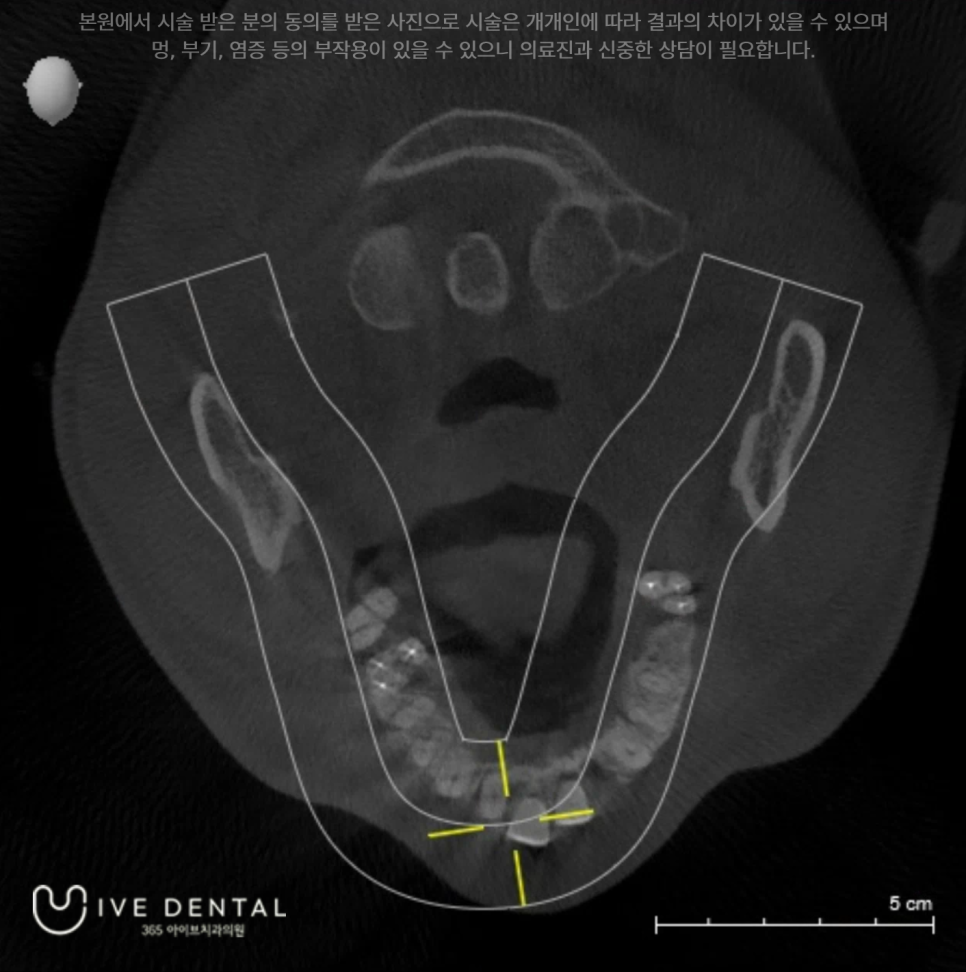

먼저 X-ray와 CT를 통해 정확한 진단을 하게 되는데요.

저희병원에서는 대학 병원급의 1억이 넘는 시로 나사의 AXEOS라는 CT를 사용하고 있습니다.

외상환자의 경우에는 무엇보다 정확한 진단이 중요한데요.

현존하는 최고 해상도의 CT를 이용하여 정확한 진단 후 치료계획을 수립하게 됩니다.

위 환자분은 사다리에서 떨어져 콘크리트에 부딪히는 큰 충격을 받은 상태입니다.

이 때문에 전치부터 치아가 파절 및 잇몸에서 탈구된 상태이며 치아 뿌리까지 이미 손상된 상황으로

즉시 응급 처치가 필요한 상황이었습니다.